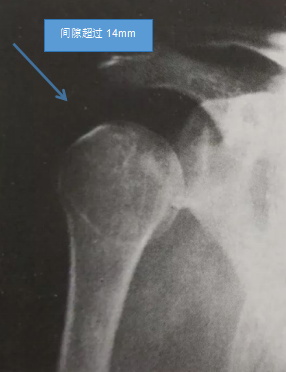

(1)X线检查:肩正位片显示肩峰与肱骨头间隙超过14mm,或两侧间隙之差>10mm。